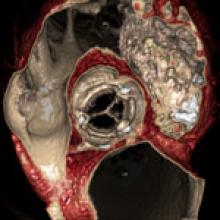

Two big advances in cardiac advanced visualization software were highlighted in December at the 2010 Radiological Society of North America (RSNA) meeting in Chicago. TeraRecon highlighted a computer-aided detection (CAD) software module to detect coronary artery stenosis.

Computed tomography (CT) technology has developed tremendously in the past 30 years. Significant improvements in spatial and temporal resolution of current scanners allow for acquisition of high-resolution images of the small and fast-moving coronary arteries.